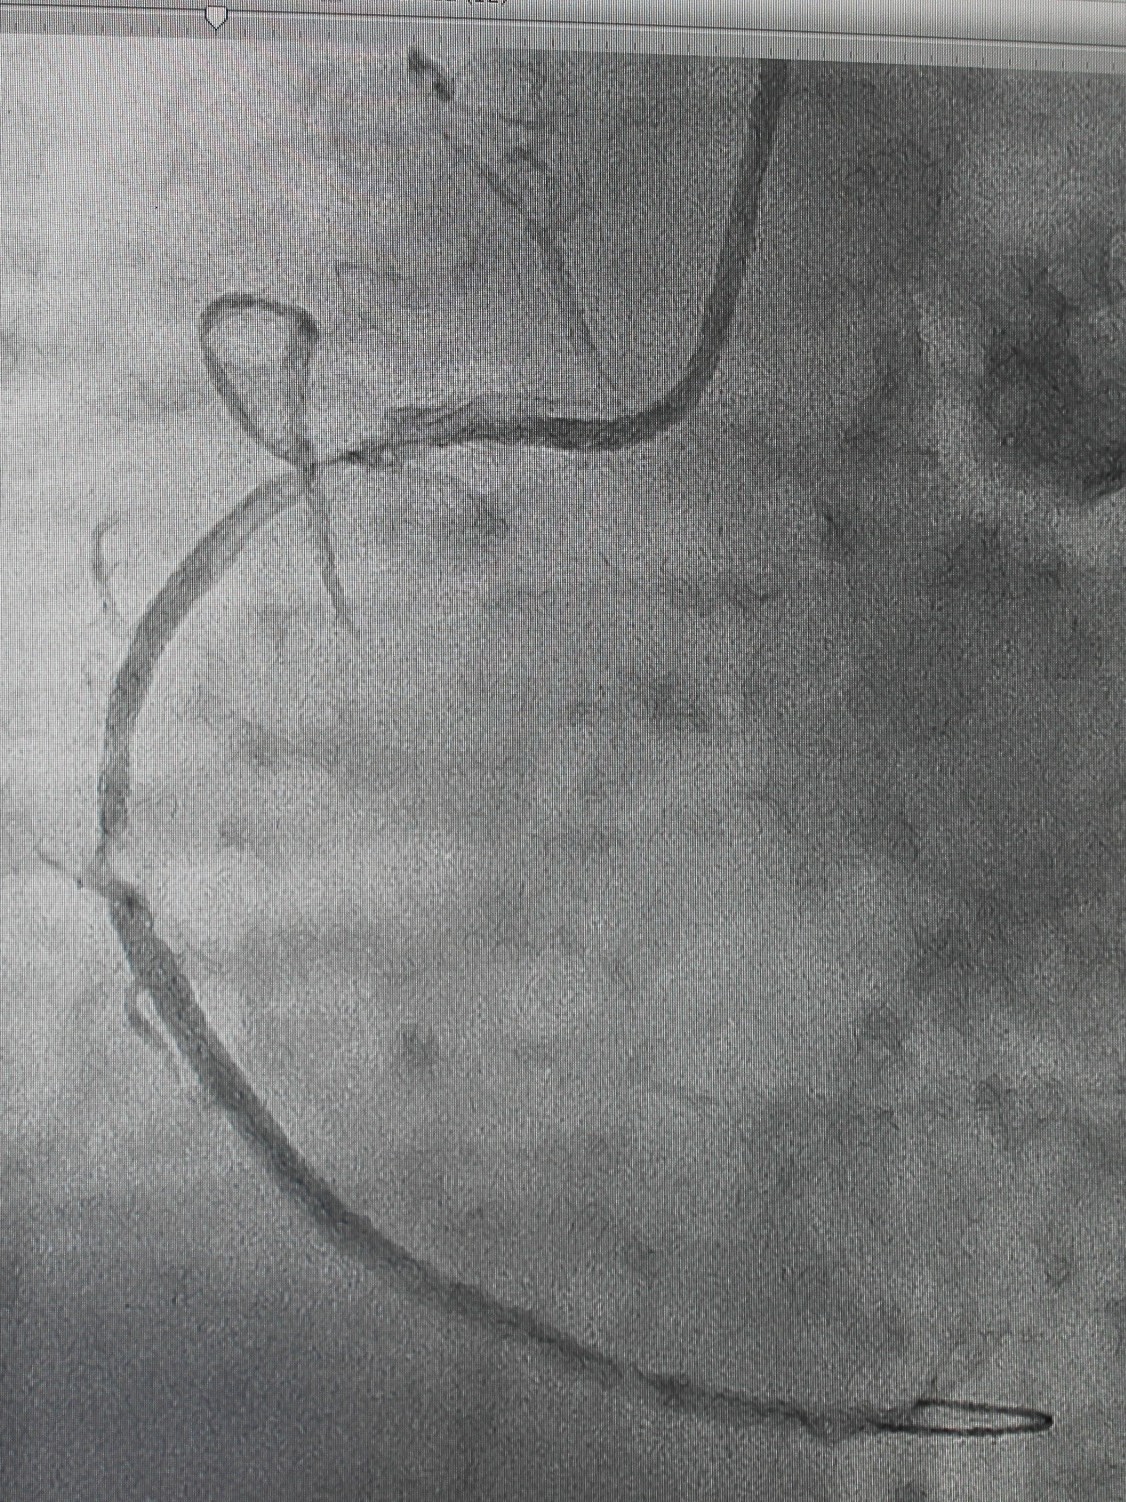

По экстренным показаниям проведена коронароангиография, выявлено стенозирующее многососудистое поражение: стеноз (сужение) передней межжелудочковой ветви левой коронарной артерии 80% в проксимальной трети, стеноз огибающей ветви 75% в дистальной трети (при том, что существенным рассматривают сужение артерии > 50%), тромботическая окклюзия правой коронарной артерии (в проксимальной трети). Рентгенхирурги выполнили тромбэкстракцию из правой коронарной артерии, баллонную ангиопластику со стентированием правой коронарной артерии (2 стента с лекарственным покрытием). Операция продолжалась около часа, после чего пациент продолжил лечение под наблюдением врачей отделения кардиореанимации; через двое суток был переведен в отделение кардиологии для дальнейшего лечения.

| Окклюзия правой коронарной артерии, кровоток отсутствует | Аспирационным катетером выполнена механическая тромбэкстракция |

| Обнаружены участки стенозирования артерии | Установлены 2 стента, стенты раскрыты | На контрольной ангиограмме: коронарный кровоток восстановлен, раскрытие стентов полное, позиционирование адекватное |